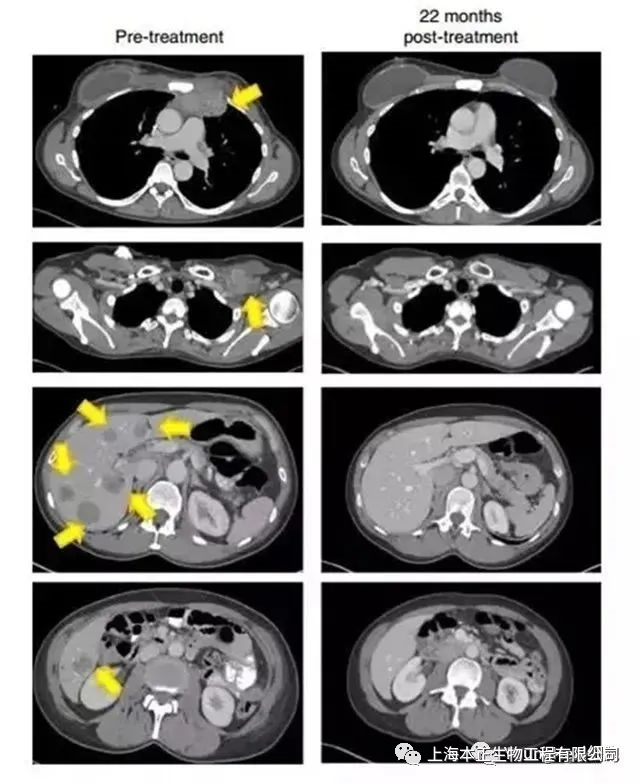

22个月后,影像检查显示(黄色箭头)肿瘤消失得无影无踪(图源:《Nature Medicine》)

四个月后,朱迪接受了900亿个有特异性杀伤能力免疫细胞的输注,一周过后,她感觉自己的身体起了明显的变化,比如胸部的肿瘤感觉逐渐缩小。又过了一两周,胸腔内的肿瘤完全消失了。

该结果对于癌症治疗领域而言,是一个历史性的突破。因为Judy Perkins已经是终末期癌症病人,相当于被传统疗法宣告了“死刑”,而细胞免疫疗法让她迎来了新生。